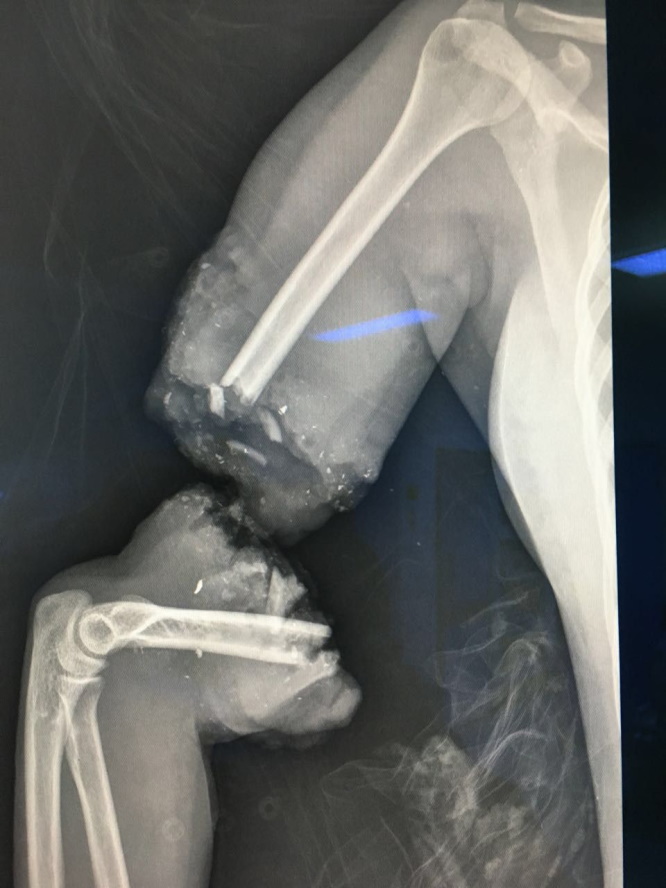

A surgical team at King Abdulaziz Hospital in Jeddah (western Saudi Arabia) was able to save a pregnant woman and her fetus after enduring a serious run-over accident while crossing a busy street on Tuesday 27th Sep, which led to the amputation of her entire arm.

Saudi Health indicated that the patient came to the hospital's emergency as a critical case that requires saving the mother and the fetus. A rapid response medical team was set, and surgery was performed to restore the amputated limb in a procedure that lasted for 6 hours, which ended with returning the arm to full functionality.